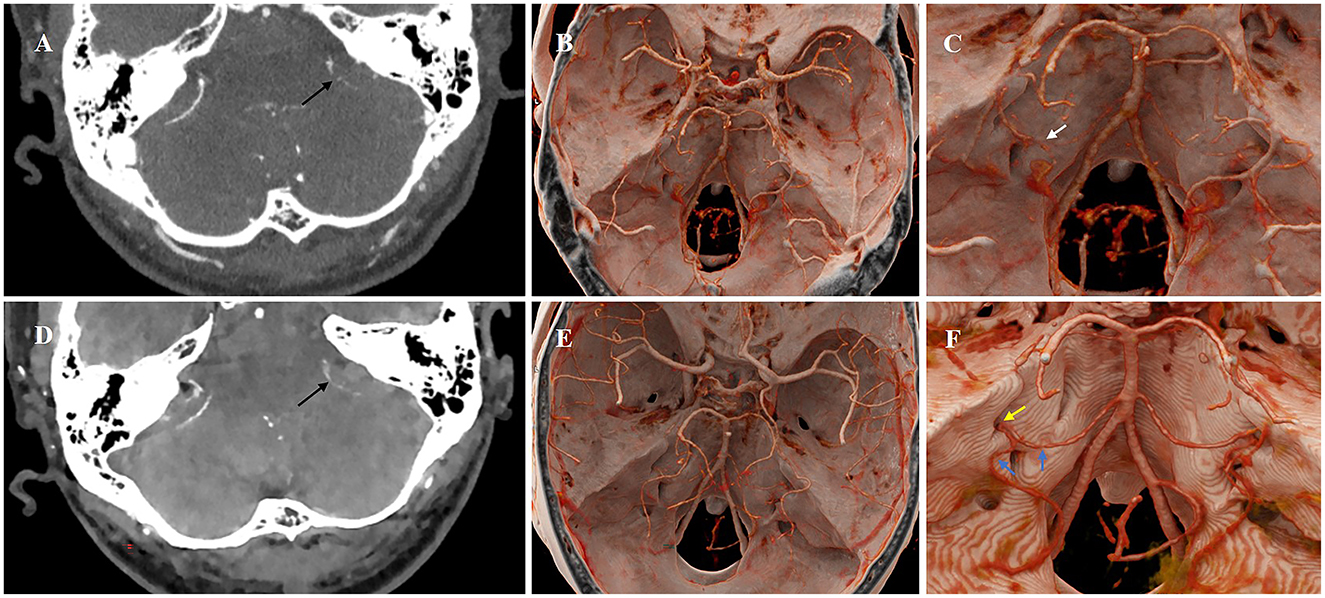

The pathophysiology of idiopathic sudden sensorineural hearing loss (ISSNHL) remains unclear. It is widely hypothesized that vascular ischemia, leading to acute labyrinthine ischemia, may represent the most probable underlying etiology. We describe a 51-year-old previously healthy man presenting with acute-onset left-sided hearing loss, tinnitus, and vertigo persisting for 24 hours. His clinical features were consistent with acute labyrinthine ischemia, suggesting this as the probable etiology of ISSNHL. Initial photon-counting CT (PCCT) of the inner ear suggested that the branches of the anterior inferior cerebellar artery (AICA) supplying the inner ear, including the labyrinthine artery, were slightly attenuated and exhibited a sparse branching pattern. Follow-up imaging after therapy within a week revealed significant improvement in both the vascular caliber and blood flow. To our knowledge, this case represents the first successful application of PCCT to directly suggest acute labyrinthine ischemia, providing the first reported radiological evidence for this mechanism.